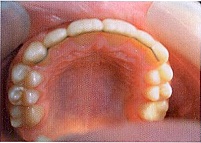

Осмотр полости рта (Рис. 2):

Рис. 2

St. localis: гематома слизистой верхней губы, отек и гиперемия слизистой в области верхних резцов, гематома в области зубов 2.2, 2.3, обратное резцовое перекрытие в области 1.1, 2.1, 2.2. Экструзия зубов 1.1, 2.1 и 2.2, подвижность зубов 1.1, 2.1 и 2.2 II степени (Рис. 3).

Рис. 3

Окклюзия: смыкание в области первых моляров и клыков по III классу. Сужение и укорочение верхнего зубного ряда, по трансверзали бугровые контакты. Обратное

резцовое перекрытие около 3 мм. Вестибулярное положение зуба 2.3.